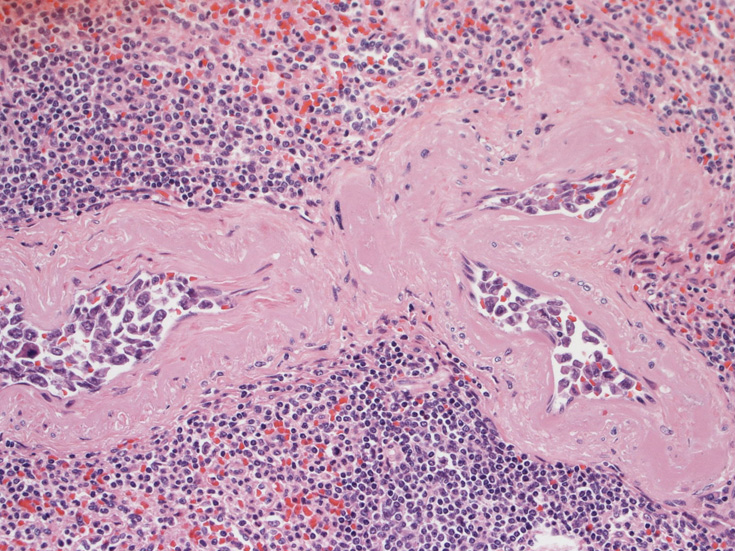

肺B;小気管支動脈, 肺動脈内を腫瘍細胞が閉塞する. 動脈内膜に浸潤性増殖している(B)。

骨髄の組織所見